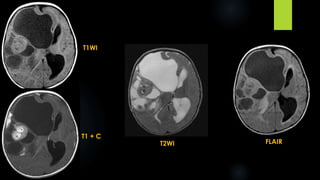

Intracranial Teratoma (contd.)

 CT:

 Intracranial teratomas are often seen as large lesions at presentation

 tumours typically demonstrating a mixture of tissue densities and signal intensity

 demonstrate at least some fat and some calcification, which is usually solid / "clump-like"

 They usually have cystic and solid components, contributing to an irregular outline.

 Solid components demonstrate variable enhancement

 MRI:

 T1 - hyperintense components due to fat and proteinaceous/lipid rich fluid; intermediate

components of soft tissue; hypointense components due to calcification and blood products

 T1 C+ (Gd) - solid soft tissue components show enhancement

 T2 - again mixed signal from differing components

T1WI

T2WI

FLAIR T1 + C

Differential diagnosis:

sPNET

ATRT

Choroid plexus carcinoma

Intracranial lipoma

Intracranial dermoid

Craniopharyngioma